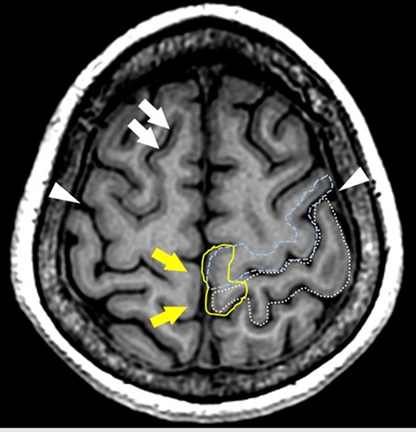

脳の中心傍小葉という部分の皮質のT1強調画像での信号が他の部分と異なるということ、その所見が中心溝の同定に有用であるということを検討しました。中心溝は一次運動野である中心前回、一次感覚野である中心後回の解剖学的な目印であり、臨床的にも重要な構造です。